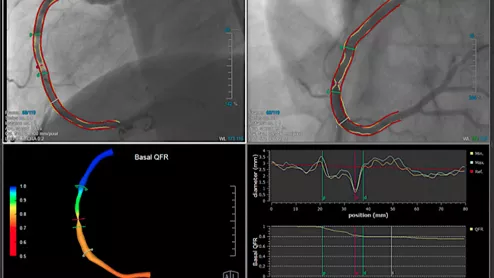

Example of QFR technology, which uses a rotation of the C-arm around the patient to create a 3D model and a color coded map showing the FFR values and drops in blood flow.

Two-year outcomes of a QFR-guided vessel and lesion selection strategy showed that the benefits of QFR guidance continued to accrue over time compared with standard angiography guidance in patients undergoing PCI.